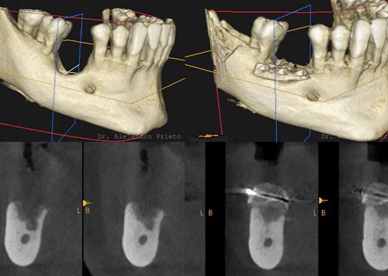

Como hemos hablado en varios post anteriores, un implante dental es una solución fija para reemplazar un diente perdido. Un implante cementado significa que la corona cerámica (el diente visible) está permanentemente unida al pilar del implante con cemento dental. Esto crea una apariencia natural y continua (sin agujeros visibles de tornillo) y una […]